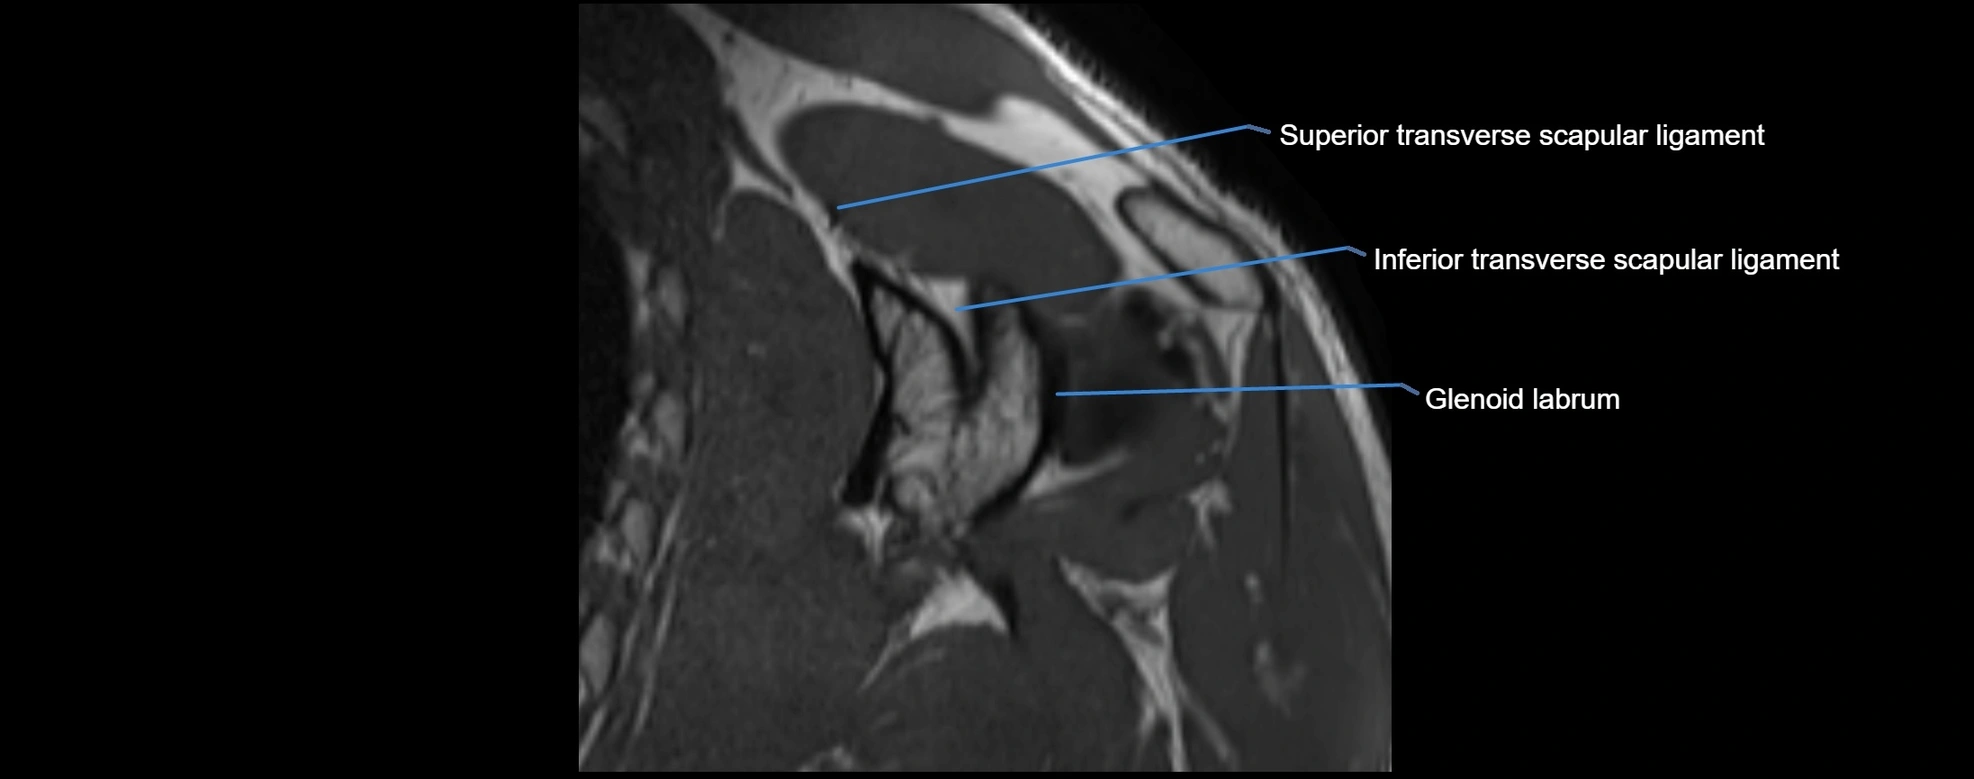

CT image

image